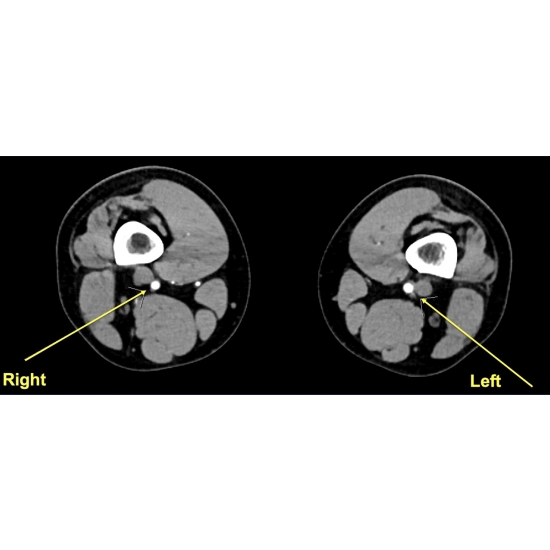

| Poor Perfusion Or Elevated Pressures? An Exertional Lower Limb Pain Conundrum - Page #3 | |||